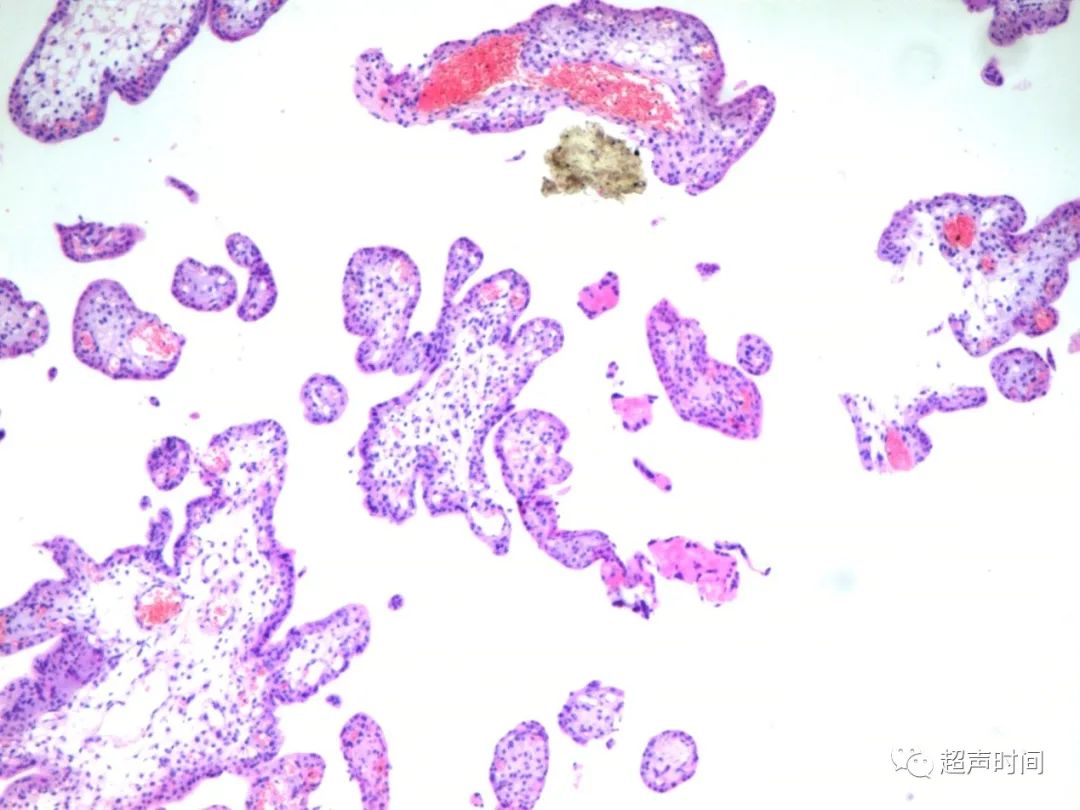

术后病理

左阔韧带送检组织中查见绒毛,符合异位妊娠(图 6 )。

图 6 术后病理提示送检组织见绒毛,符合异位妊娠